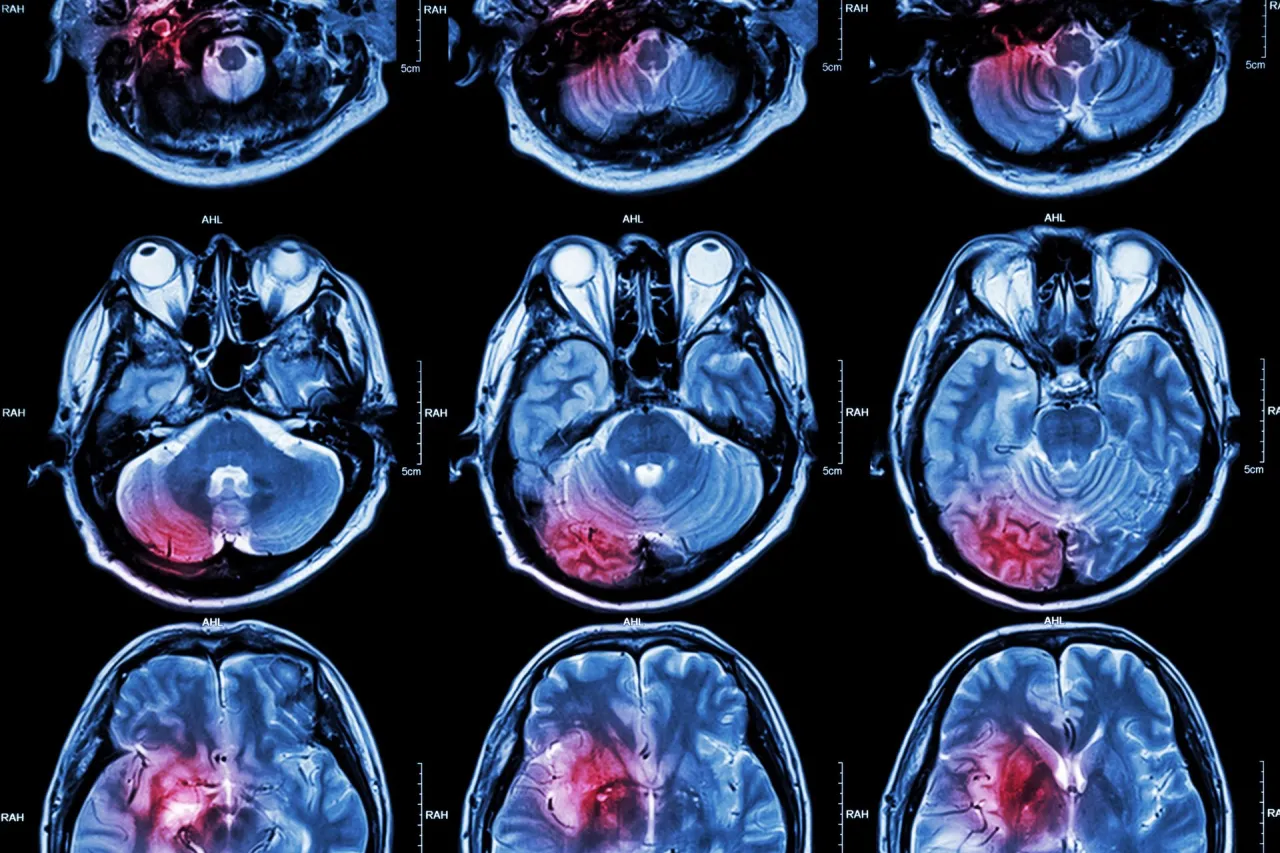

- W ostrej fazie udaru kluczowa jest tomografia komputerowa (TK) głowy, pozwalająca odróżnić udar niedokrwienny od krwotocznego.

- Rezonans magnetyczny (MRI) oferuje dokładniejszy obraz, ale jest dłuższy i mniej dostępny w nagłych przypadkach.

Tomografia komputerowa (TK) głowy bez kontrastu to badanie pierwszego wyboru w diagnostyce udaru. Dlaczego? Jest niezwykle szybkie i ogólnodostępne. Pozwala natychmiast wykluczyć krwawienie śródmózgowe, co jest kluczowe w odróżnieniu udaru krwotocznego od niedokrwiennego. Chociaż wczesne objawy udaru niedokrwiennego mogą nie być od razu widoczne na TK, to właśnie wykluczenie krwawienia pozwala na podjęcie decyzji o wdrożeniu leczenia trombolitycznego, jeśli pacjent znajduje się w oknie terapeutycznym. Wynik TK jest zatem decydujący dla podjęcia dalszych kroków terapeutycznych.Rezonans magnetyczny (MRI): Kiedy potrzebne jest dokładniejsze spojrzenie na mózg?

Rezonans magnetyczny (MRI) jest badaniem znacznie dokładniejszym niż TK, szczególnie w wykrywaniu wczesnych, drobnych zmian niedokrwiennych oraz ocenie rozległości udaru. Stosuje się go zazwyczaj, gdy obraz TK jest niejednoznaczny, w późniejszej fazie diagnostyki, lub w przypadku udarów o niejasnej przyczynie, na przykład u młodych pacjentów. MRI pozwala na szczegółową ocenę uszkodzeń tkanki mózgowej, co jest ważne dla planowania dalszej rehabilitacji. Warto jednak pamiętać o jego ograniczeniach: MRI trwa dłużej i jest mniej dostępne w trybie pilnym niż TK, co sprawia, że nie jest badaniem pierwszego wyboru w ostrej fazie udaru.